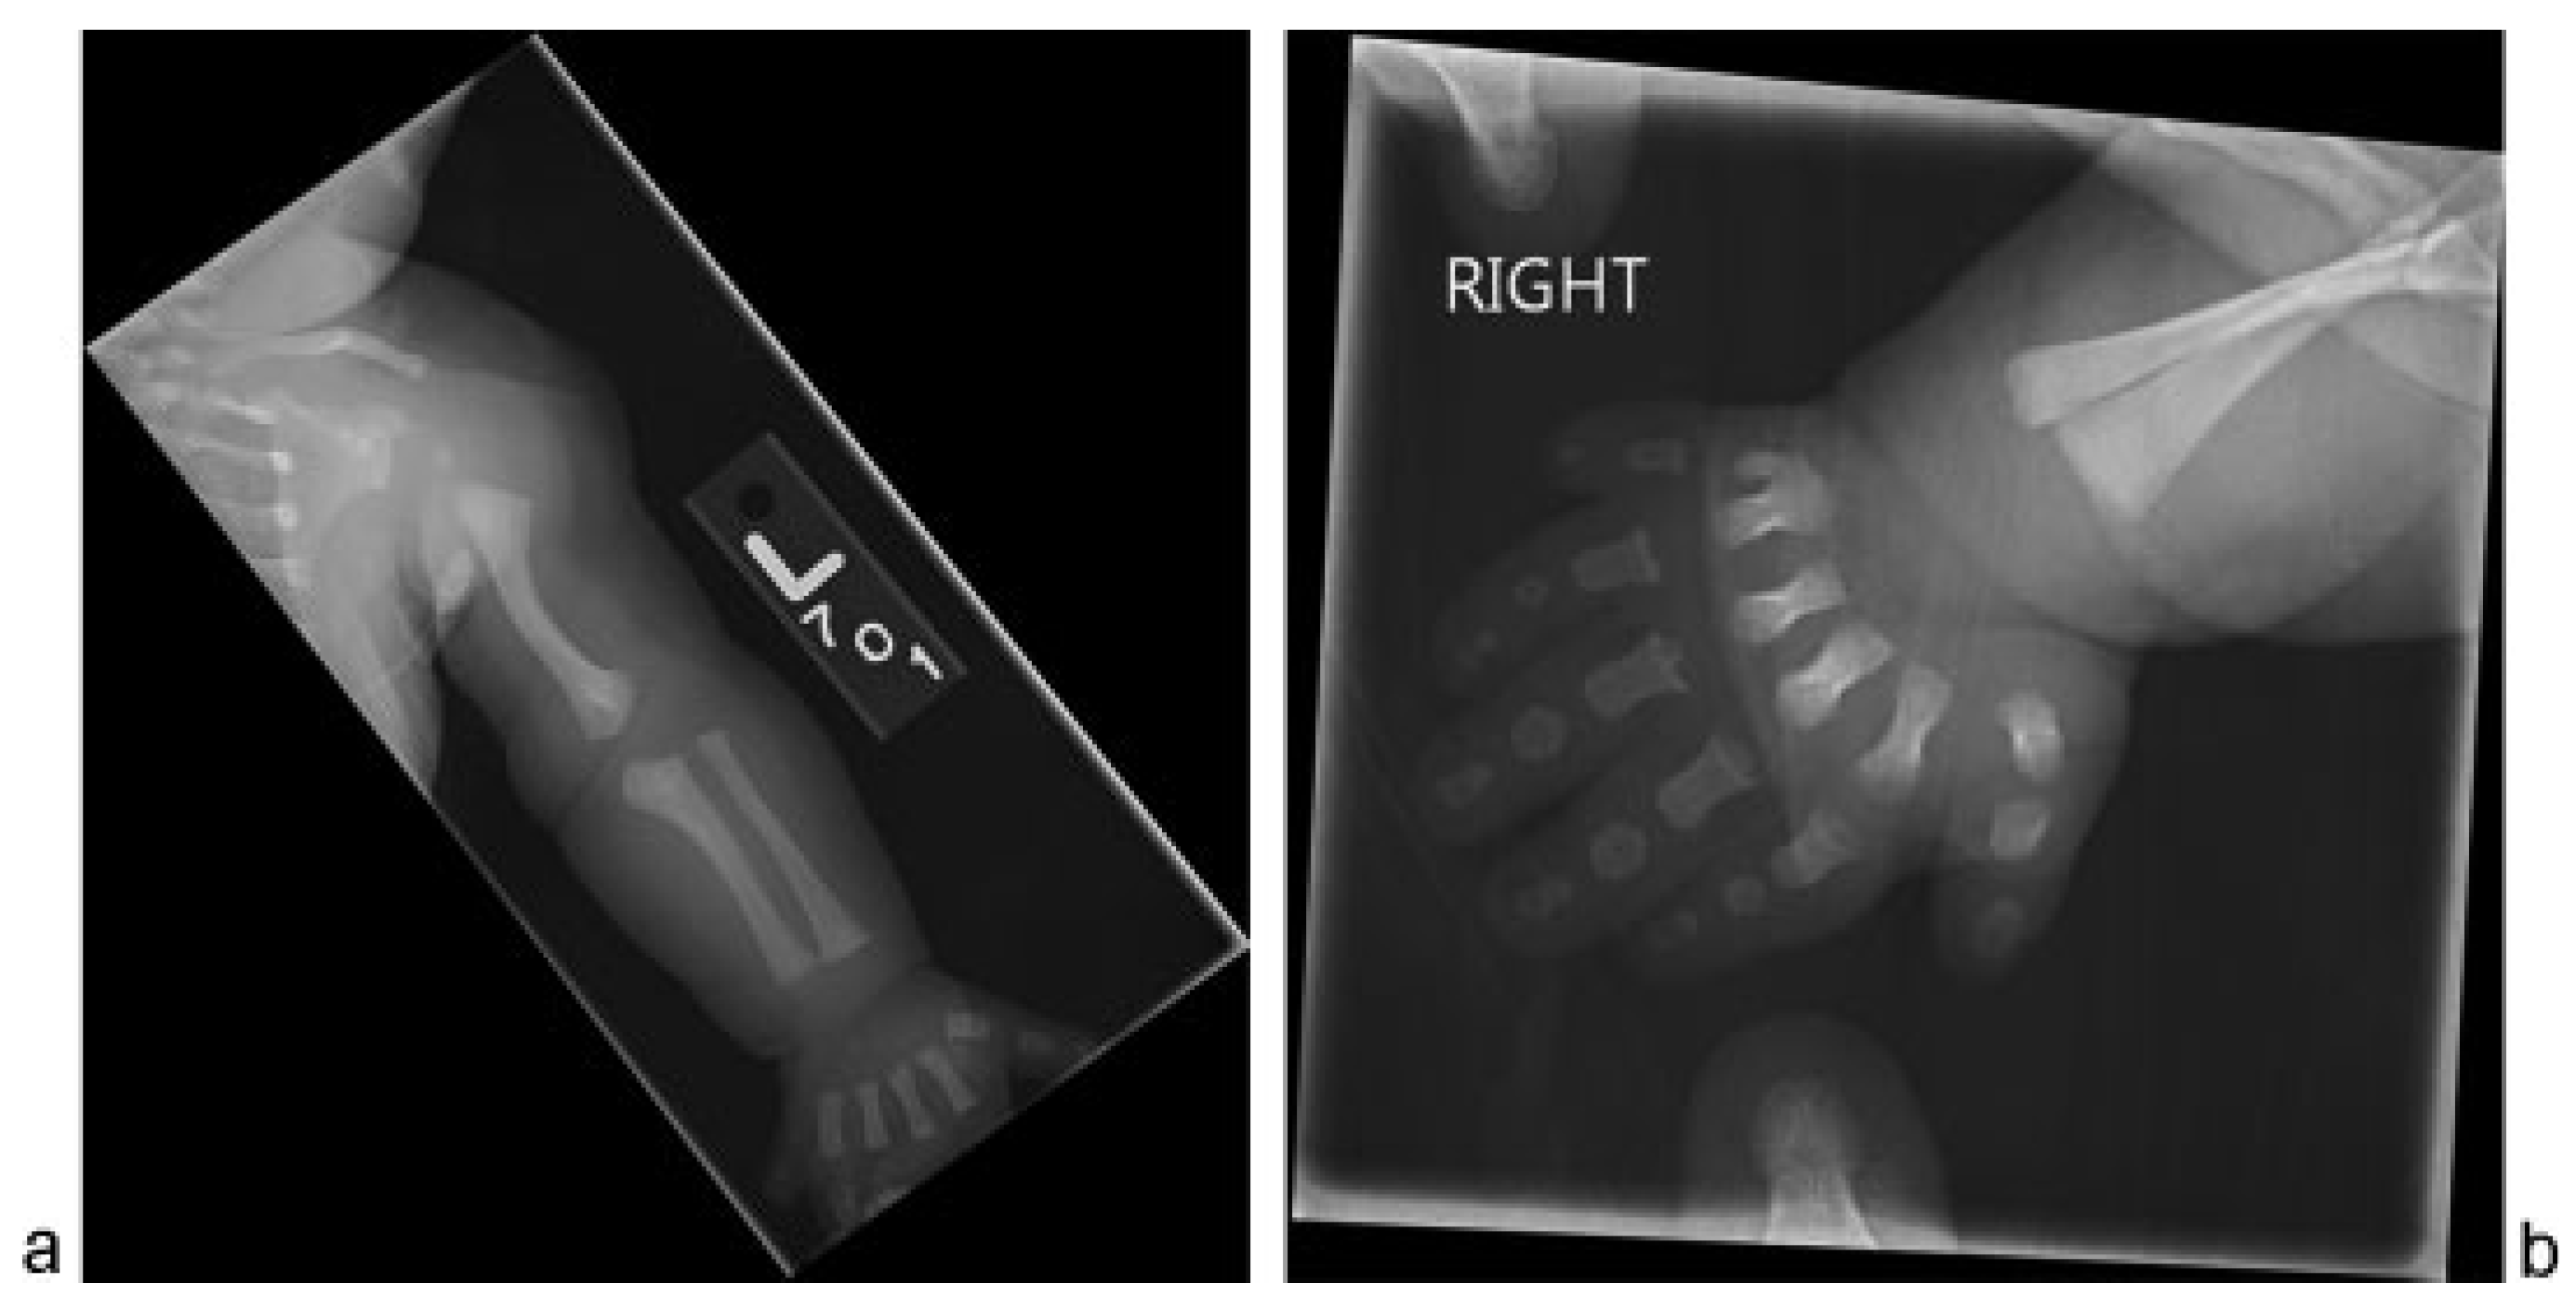

Skeletal survey confirmed sagittal craniosynostosis and a posterior parietal buckle fracture (Figure 1). Shortening and mild angular deformities of the bilateral ribs were noted. Upper extremities showed bilateral valgus deformities of the humeri, varus deformities of the proximal ulnas, radial head dislocations, and postaxial polydactyly exhibiting fusion at the base of the fifth and sixth metacarpals (Figure 2). Lower extremities showed bilateral mild varus deformities of the femurs, meso-melic shortening, relative overgrowth of the fibulas, and mild brachydactyly (Figure 3). An echocardiogram confirmed a moderately dilated and hypertrophied right ventricle with normal systolic function and revealed a small patent ductus arteriosus and a small secundum atrial septal defect.

Figure 2. Skeletal survey. (a) Left upper extremity demonstrates valgus deformity of the humerus, varus deformity of the proximal ulna, radial head dislocation and postaxial polydactyly, similar findings were seen on the right. (b) Right hand demonstrates postaxial polydactyly with fusion at the base of the 5th and 6th metacarpals.